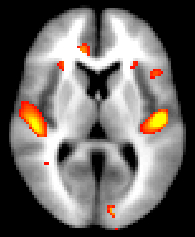

We strongly recommend using randomise (permutation testing) for inference in VBM-style analysis and not Gaussian random field theory (GRF), as the approximations underlying the latter are not generally appropriate in such analyses.

Running randomise and displaying TFCE-based thresholding results

Having chosen the most appropriate smoothing (e.g. sigma = 3mm), run randomise (see randomise usage), for instance:

You can then view the (1-p) corrected p-value images in FSLView:

Running randomise and displaying cluster-based thresholding results

Once you have chosen the most appropriate smoothing (e.g. sigma = 3mm) and threshold (e.g. t > 2.3) for the cluster-based correction, then feed them into a full run of randomise (see randomise usage), for instance:

Then you can threshold your _clustere_corrp_ images (corrected p-values maps) at 0.95 to keep only the significant clusters and use it to mask the corresponding tstats map:

fslmaths fslvbm_clustere_corrp_tstat1 -thr 0.95 -bin mask_pcorrected

fslmaths fslvbm_tstat1 -mas mask_pcorrected fslvbm_tstat1_corrected

before displaying it with fsleyes overlaid on the template_GM or the MNI152 template for example:

To report information about clusters in the results from randomise, see the cluster tool.